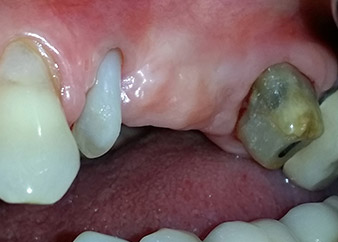

A 58-year-old female patient complained of pain and increased mobility of her bridge abutment tooth 24. Periodontal inflammation was present with pocket depths of 7 mm mesiobuccally and more than 12 mm distally, as well as third-degree furcation involvement. Moreover, the radiograph revealed an extensive periodontal lesion around the apical region of the (alio loco) endodontically pretreated tooth 24 (Fig. 1).

One year earlier, teeth 25 and 26 had been extracted due to trauma and for endo-perio reasons, prior to the placement of the bridge. A combined endo-perio lesion was diagnosed for tooth 24, of unclear aetiology. The patient wanted to keep her bridge abutment teeth 24 and 27 and would not accept a final, or even temporary, removable prosthesis. Therefore, it was agreed to make all efforts to retain both teeth, in spite of their poor prognosis as based on radiological and clinical findings.

Placement of two submerged implants was planned at sites 25 and 26, in a surgical session with open periodontal debridement and apicoectomy of tooth 24. Due to the vertical bone deficiency at the future implant site, an internal sinus augmentation was also planned.

Figures 17 and 18 show the clinical result two months after the surgery. Tooth 24 exhibited reduced mobility of Miller class 1, and the soft tissues were free of inflammation. Probing was avoided at this point of time to prevent reinfection and to avoid violating the epithelial attachment. A control visit was scheduled for reentry and placement of healing abutments, six months after the insertion of the implants.

Two months after the surgery, the patient was pain-free.

Fig. 17: Two months after the surgery, the patient was pain-free and the area was free of inflammation.

after the surgery

Fig. 18: Tooth 24 now showed less mobility.